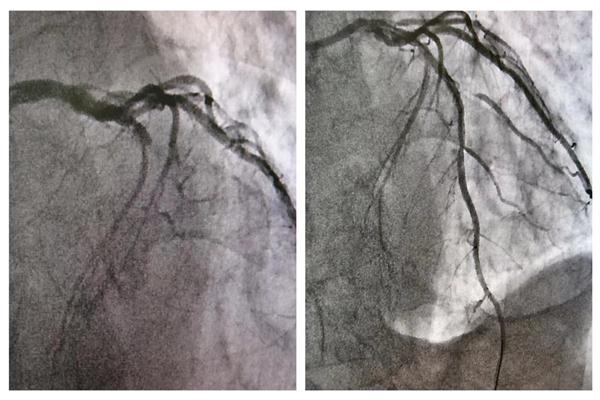

17:22患者抵达导管室行急诊冠脉造影+介入治疗,术中造影显示,犯罪血管为“前降支7段近端”呈100%闭塞,患者病情危重,没有一刻停留和犹豫,介入团队在尹哲主任的带领下紧张有序、团结协作、快速处置,17:50导丝通过闭塞段,血流恢复,行药物球囊扩张病变处,无夹层及血栓形成,手术顺利结束。术后患者胸痛消失,心率血压平稳,目前,在医师指导下,患者已能下床适度活动,再无胸痛症状反复,生命体征正常。